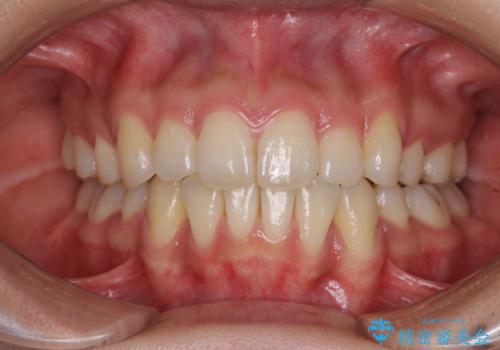

- 以前の矯正治療の後戻りにより、上下の前歯がでこぼこになってしまったことを気にして来院された患者様です。

口元がこれ以上突出することなく前歯の叢生が改善できるよう、歯と歯の間を削ってスペースを獲得し、インビザラインを用いて整えていくこととしました。

目安の装着時間である1日22時間をしっかりと実践してくださり、半年強という短期間で治療を終えることができました。